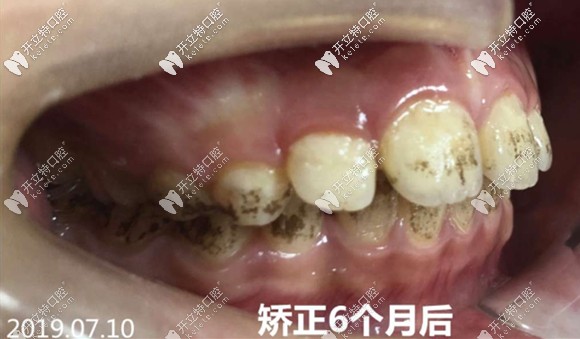

<矯治半年后的牙齒側(cè)貌~~~還好這位明智的家長將孩子的齙牙凸嘴扼殺在萌芽期,僅僅半年就變化驚人>

矯治6個月后的牙齒側(cè)貌圖